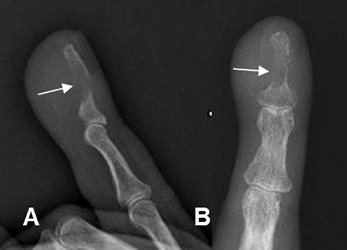

Fig 27 B. Osteomielitis.

A: Rx lateral y B: Rx AP: Prominencia de los tejidos blandos y lesión lítica en la falange distal, por osteomielitis.